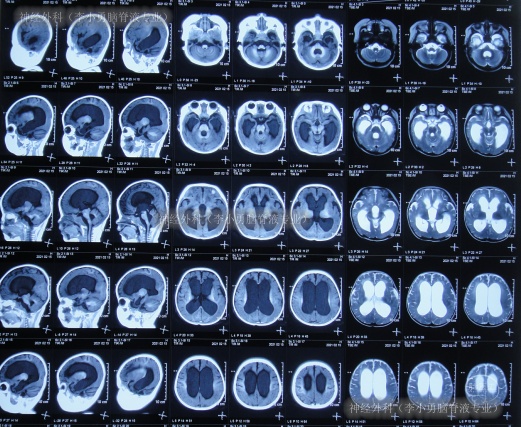

给予抗感染治疗后体温虽很快降至正常,但2021年2月6日,意识变差,意识模糊,查头颅MRI(图-3)示脑积水,鞍上池、四脑室周围及部分脑沟、裂周围脑膜强化结果;脑室穿刺术,脑脊液蛋白高。

图-3:2021年2月6日头颅MRI